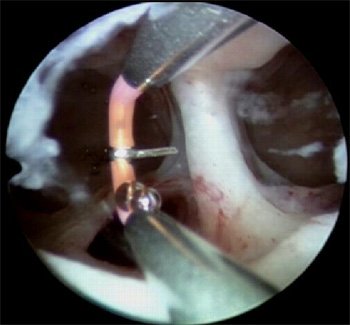

Die hysteroskopische Endometriumablation ist ein operatives Verfahren zur Behandlung von Blutungsstörungen. Ziel der Operation ist es, die Gebärmutterschleimhaut (Endometrium) komplett und dauerhaft zu entfernen. Im Gegensatz zu der häufig durchgeführten "Ausschabung" (Abrasio) handelt es sich bei der Endometriumablation um einen technisch aufwändigeren, allerdings für die Patientin wenig belastenden Eingriff. Während eine "Ausschabung" mittelfristig nur selten zu einer Verringerung der Regelblutung (Menstruation) führt, soll durch die Endometriumablation möglichst eine komplette Blutungsfreiheit (Amenorrhoe) erreicht werden. Die Operation wird mit einem sogenannten Resektoskops durchgeführt, das aus einem optischen System mit integriertem Schneidemechanismus besteht. Dieses Instrument wird von der Scheide aus durch den Gebärmutterhals in die Gebärmutterhöhle eingeführt. Dort wird die Gebärmutterschleimhaut systematisch und entsprechend tief abgetragen, so dass eine Regelblutung danach allenfalls in einer sehr abgeschwächten Form wieder auftreten kann.

Die Endometriumablation stellt besonders für die Patientinnen eine Behandlungsmöglichkeit dar, bei denen bisher keine eindeutige Ursache für die belastend starken Blutungen gefunden wurde und bei denen medikamentöse Behandlungsversuche nicht den gewünschten Erfolg erzielt haben oder bei denen hormonelle Therapien nicht in Frage kommen. Voraussetzung für die Operation ist, dass kein weiterer Kinderwunsch besteht. Schwangerschaften können zwar selten auch nach einer Endometriumablation eintreten, werden aber häufig mit Komplikationen verbunden sein. Aus diesem Grunde sollte im Zusammenhang mit einer Endometriumablation auch die Frage der langfristigen Verhütungsmethode (Kontrazeption) besprochen werden. Wie bei jeder anderen Operation können auch bei einer Endometriumablation in seltenen Fällen Komplikationen eintreten oder später mit der Operation verbundenen Beschwerden entstehen. Diese, wie auch die Behandlungsalternativen, sollten vor der Operation in einem persönlichen Gespräch mit dem Operateur besprochen werden.